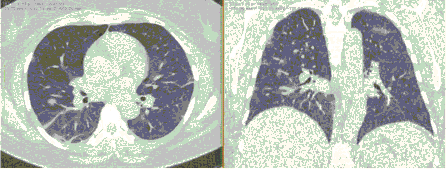

КТ имеет высокую чувствительность в выявлении изменений в легких, характерных для COVID-19. Применение КТ целесообразно для первичной оценки состояния ОГК у пациентов с тяжелыми прогрессирующими формами заболевания, а также для дифференциальной диагностики выявленных изменений и оценки динамики процесса. КТ позволяет выявить характерные изменения в легких у пациентов с COVID-19 еще до появления положительных лабораторных тестов на инфекцию с помощью МАНК. В то же время, КТ выявляет изменения легких у значительного числа пациентов с бессимптомной и легкой формами заболевания, которым не требуется госпитализация. Результаты КТ в этих случаях не влияют на тактику лечения и прогноз заболевания при наличии лабораторного подтверждения COVID-19. Поэтому массовое применение КТ для скрининга асимптомных и легких форм болезни не рекомендуется. При первичном обращении пациента с подозрением на COVID-19 рекомендуется назначать КТ только при наличии клинических и инструментальных признаков дыхательной недостаточности (SpO2 < 95%, ЧДД > 22).

3. Применение лучевых методов у пациентов с симптомами ОРВИ легкой степени тяжести и стабильном состоянии пациента, возможно только по конкретным клиническим показаниям, в том числе при наличии факторов риска, при условии достаточных технических и организационных возможностей. Методом выбора в этом случае является КТ легких по стандартному протоколу без внутривенного контрастирования или РГ при ограниченной доступности КТ. Использование УЗИ в этих случаях нецелесообразно. Применение КТ исследования в сроки ранее 3 - 5 дней с момента появления симптомов заболевания, а также при отсутствии клинических проявлений поражения бронхолегочной системы является нецелесообразным. Выполнение КТ целесообразно при наличии клинических и инструментальных признаков дыхательной недостаточности (SpO2 < 95%, ЧДД > 22), либо при дифференциальной диагностике с другим заболеванием.

- выполнение КТ легких без внутривенного контрастирования в стационарных условиях или в амбулаторных - при показаниях к госпитализации;